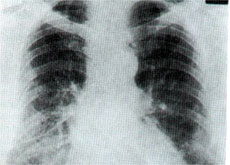

Radiografia di polmoni colpiti da asbestosi (foto Internet)

Una catastrofe, un dramma senza fine di cui poco si parla. Ma a Casale Monferrato, una zona più conosciuta per il vino e la buona cucina, da anni si muore di mesotelioma. Un male terribile che colpisce la pleura, dovuto alla contaminazione da amianto.

In famiglia, quotidianamente ognuno aveva la sua dose di veleno. Dopo 15-20 anni di incubazione, operai ma anche le mogli e i figli si ritrovano il male dentro i polmoni.